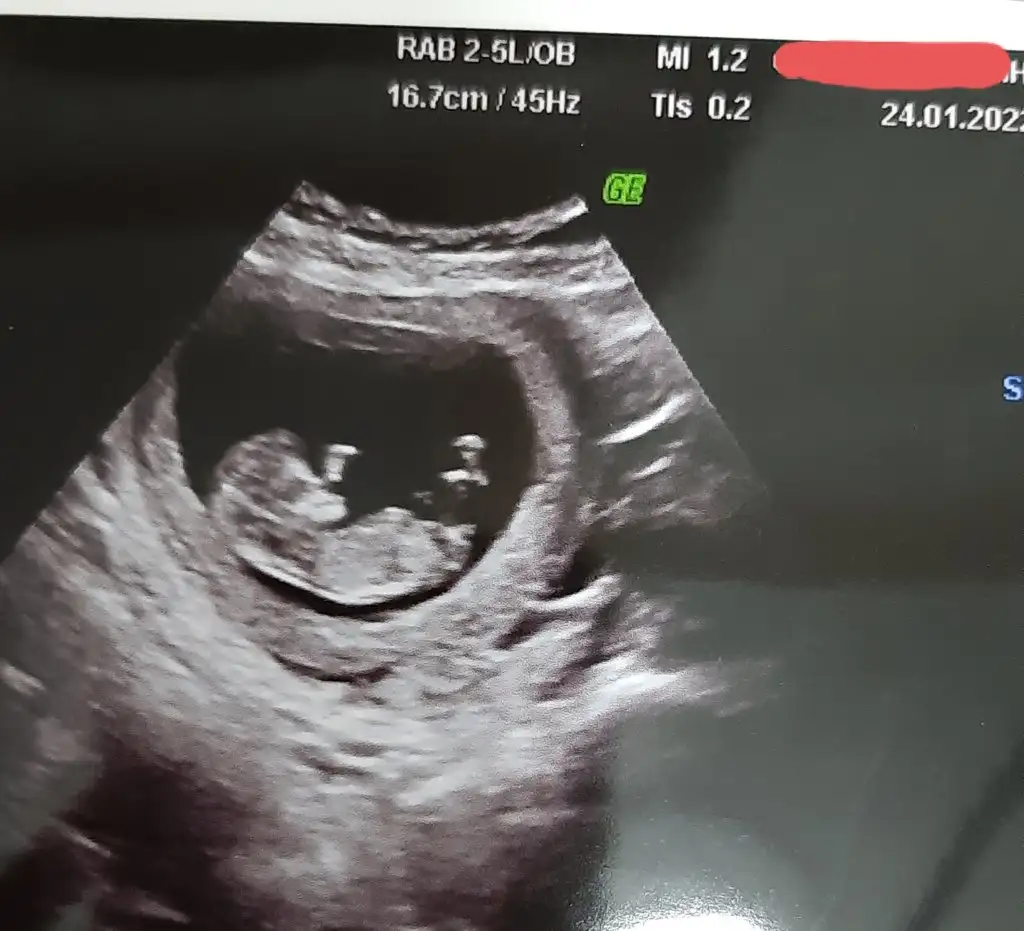

dr soylemeden siz gorun genital nub teorisi ( bebegin cinsiyeti)

Benide tahmin efermisiniz

• 20220124_204527.webp

21 KB · Görüntüleme: 61